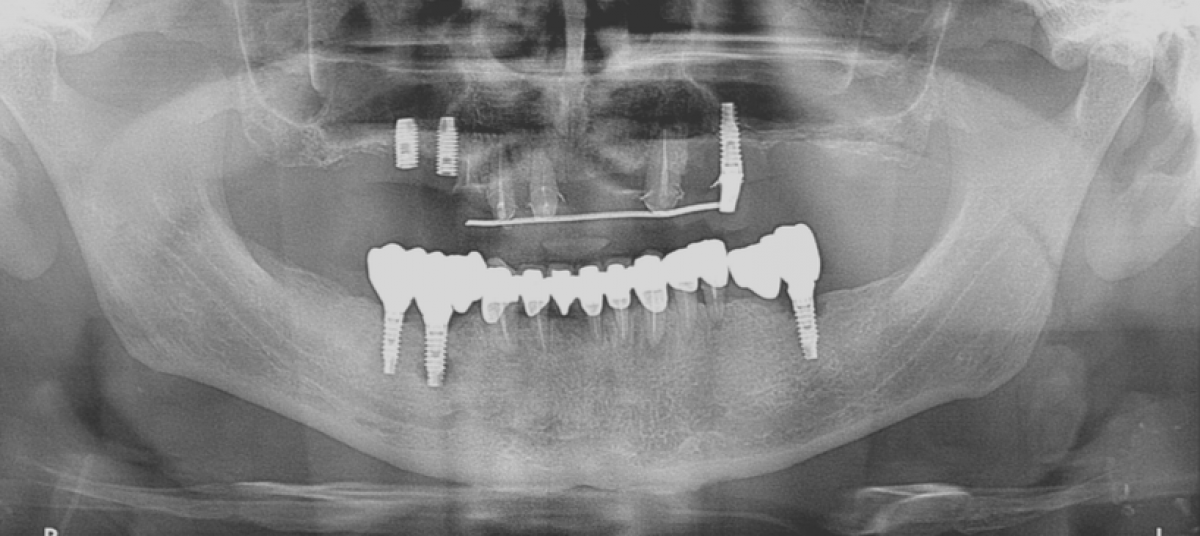

All the inserted implants have now reached an insertional torque sufficient enough to perform an immediate loading. FIG 8

At the end the screwed temporary restoration is fixed with metal-metal cement at the abutments in oral cavity to ensure the passivation. FIG 9